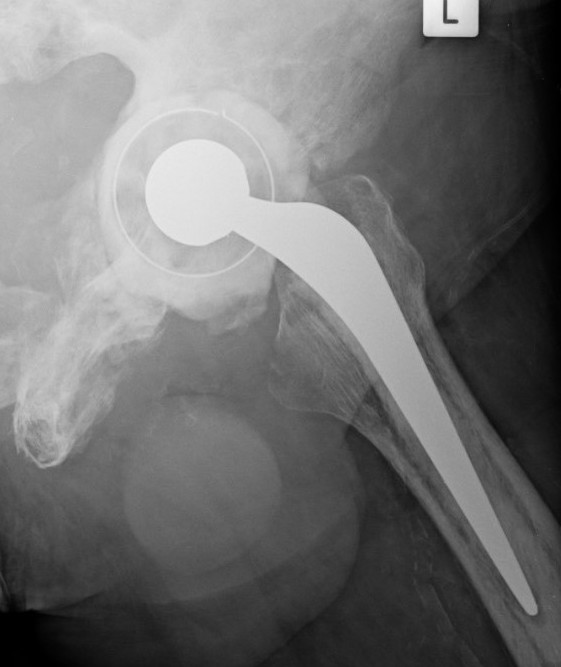

THA

Technical issues

Femur

- coxa vara - risk varus femoral implants

- difficulty broaching femur - may need burrs

- femoral bowing - may need osteotomy

- poor cement interdigitation - uncemented stems may be preferred

- brittle bone - increased risk fracture